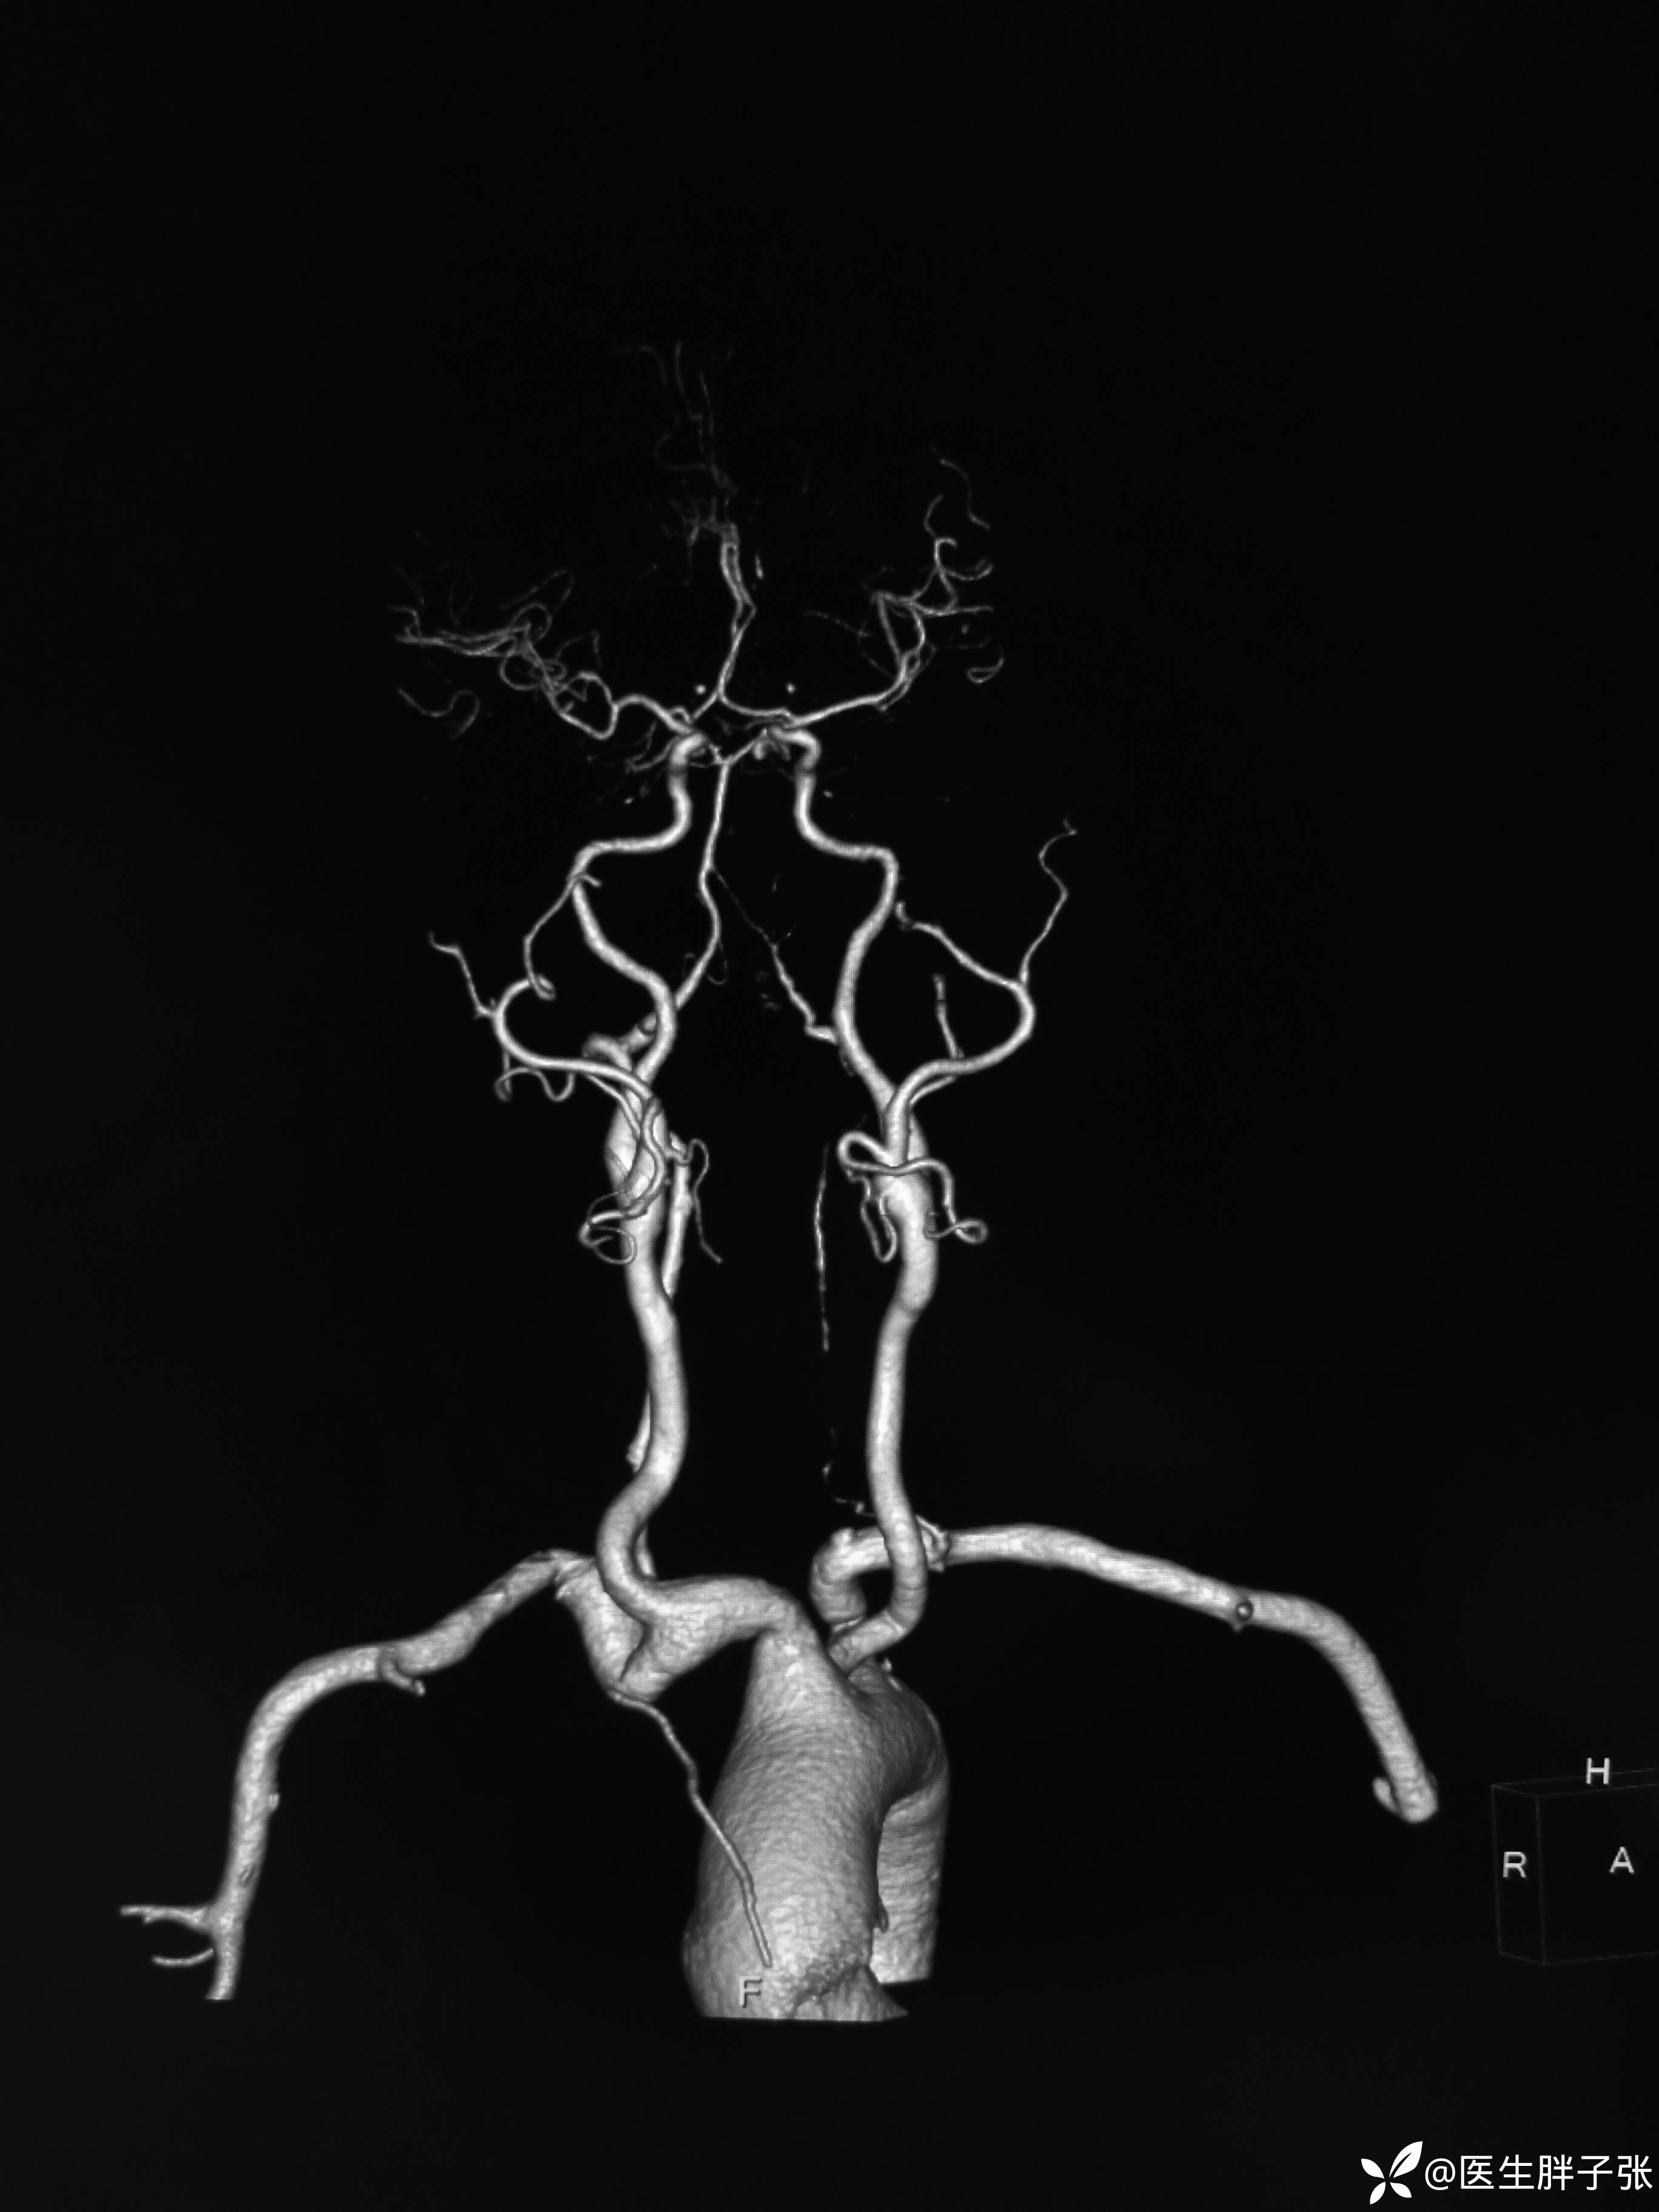

头颈部CTA提示左侧椎动脉闭塞、右侧椎动脉开口中度狭窄、左侧颈内动脉动脉瘤。